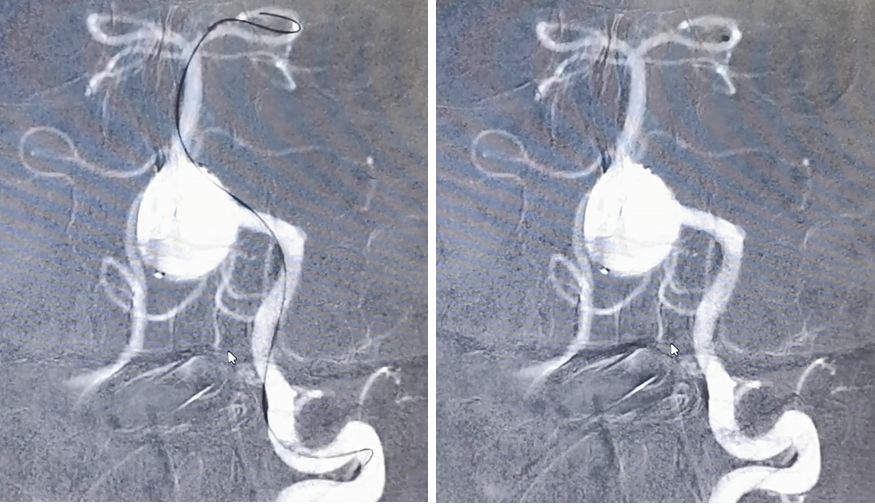

先用Synchro-200携Echelon-10由右椎动脉进入动脉瘤腔,微导管在瘤腔内盘圈,可以在输送弹簧圈的时候使弹簧圈分布更均匀

经右椎动脉逐步填塞大弹簧圈进入动脉瘤(Microplex-18系列),逐步将动脉瘤疏松填塞。期间微导管头端受到弹簧圈阻力,会缓慢回撤,此时不必刻意调整微导管再次深入动脉瘤腔内,因为我们最主要目的不是严密填塞动脉瘤—那是PED的任务—而是闭塞右侧椎动脉

最后,用小弹簧圈完全闭塞右侧椎动脉(PICA以远)